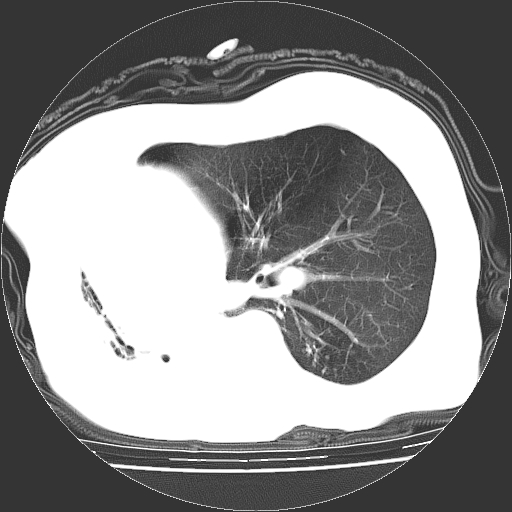

标题: CT23991:女,72岁,咳嗽、憋气一周。 [打印本页]

女,72岁,咳嗽、憋气一周,十年前曾患肺结核及胸膜结核。

右侧毁损肺,右侧纵隔疝

右侧毁损肺,右侧纵隔疝,左肺代偿!

1.右侧损毁肺伴胸膜钙化,2.左肺小结节灶,良性可能大,注意复查。3.肝脏左叶囊肿。4.先天性一侧肺不发育待出外(右侧胸廓无明显塌陷)。对比原片应该非常有帮助。